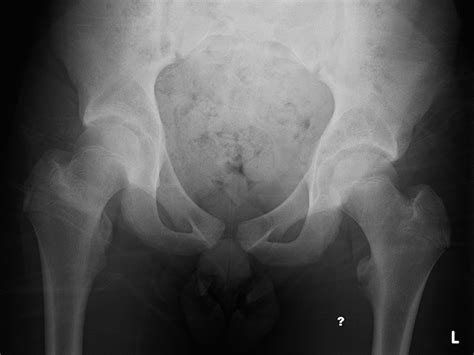

The Pelvis and Hip

The Pelvis and Hip from www.imageinterpretation.co.uk

Anteroposterior radiograph of a right hip anterior ...

Anteroposterior radiograph of a right hip anterior ... from www.researchgate.net